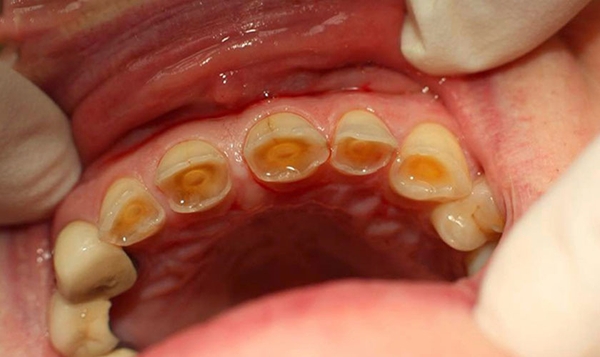

Đây là yếu tố quan trọng nhất quyết định chi phí. Mòn răng có thể được phân loại từ nhẹ đến nặng:

Mòn trung bình: Đã ảnh hưởng đến ngà răng, gây ê buốt đáng kể. Có thể cần trám răng phức tạp hơn hoặc bọc sứ.

Mòn nặng: Đã ảnh hưởng đến tủy răng, gây đau nhức dữ dội, có nguy cơ nhiễm trùng. Có thể cần điều trị tủy, sau đó phục hình bằng mão răng (bọc sứ) hoặc thậm chí nhổ răng và làm cầu răng/implant nếu răng không thể giữ lại.